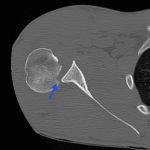

Radiographs demonstrated posterior displacement of the humeral head on the “Y” view (see white arrow) and widening of the glenohumeral joint space on anterior-posterior view (see red arrow). The findings were consistent with posterior dislocation and a Hill-Sachs type deformity.  Sedation was performed and reduction was attempted using external rotation, traction counter-traction. An immediate “pop” was felt during the procedure. Post-procedure radiographs revealed a persistent posterior subluxation with interlocking at posterior glenoid. CT revealed posterior dislocation with acute depressed impaction deformity medial to the biceps groove with the humeral head perched on the posterior glenoid, interlocked at reverse Hill-Sachs deformity (see blue arrow).